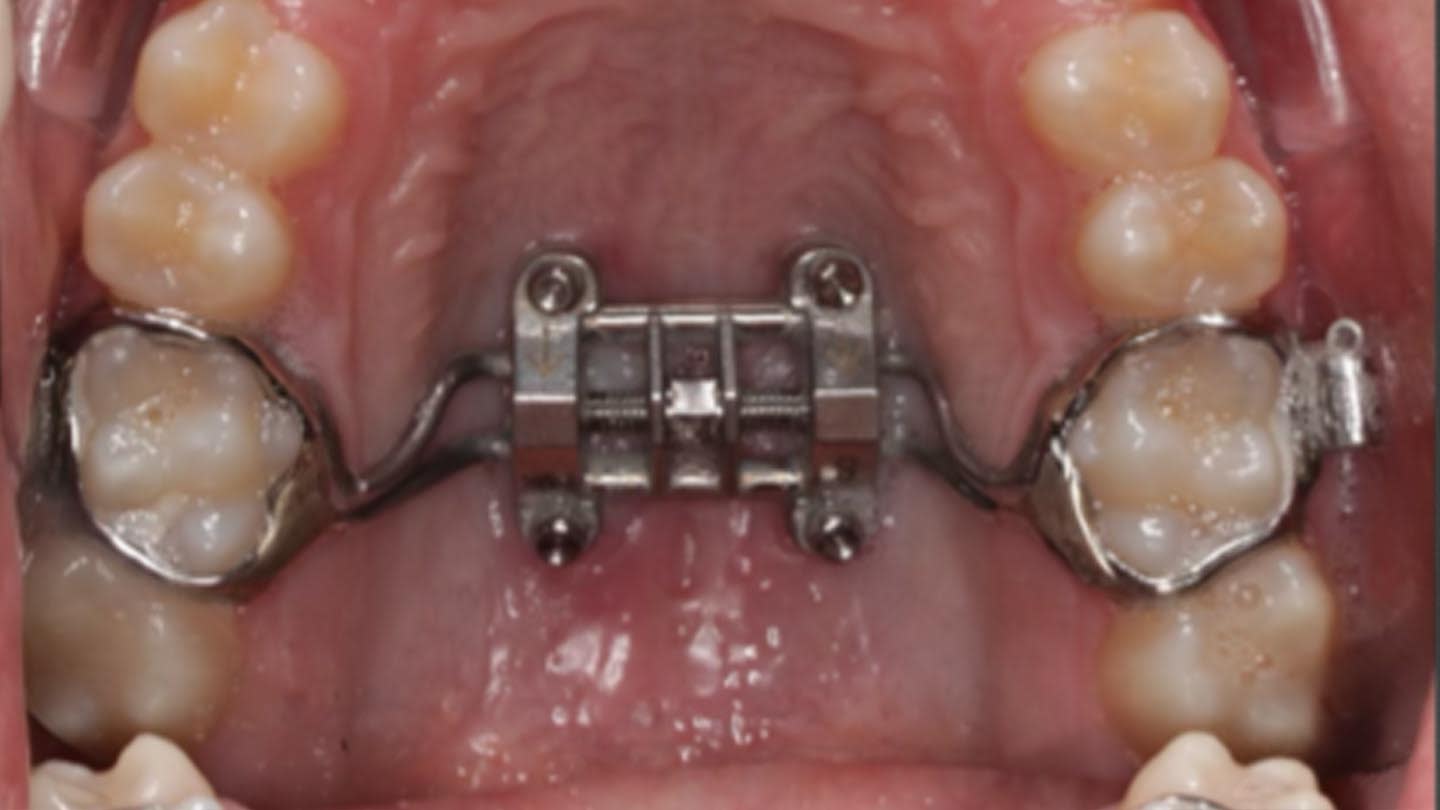

Using the miniscrew-assisted rapid palatal expansion (MARPE) technique, this expansion may be applied to female patients aged 14 to 15 years and male patients aged 16 to 17 years. The design of the skeletal expander in MARPE consists of two to four miniscrews, with the planning of the screw placement varying in direction depending on the amount of bone available, which may be monocortical, bicortical, or even tricortical, for the anchorage of the miniscrews.4,9-11

The predominant expander design was a Hyrax-type model, dentally supported on the molars and skeletally anchored by means of four miniscrews.25-28,33 Four studies used the maxillary skeletal expander (MSE) model,19,31,32,34 and one study employed a different model—the Dutch Maxillary Expansion Device (D-MED).30

Regarding the number of miniscrews used for anchorage, all studies except one used four miniscrews with a diameter of 1.8 mm and a length that varied according to each patient, while in one study, two miniscrews of 12 mm length and 1.5 mm diameter were used.29

Despite variability in appliance design, all studies reported favorable outcomes with skeletal expanders for addressing transverse deficiencies in young adults. A case presentation illustrating treatment in a 16-year-old patient is shown in Figure 2 through Figure 39. (An additional case presentation may be viewed at compendiumlive.com/go/cced2110.) The studies also agree on the importance of individualizing miniscrew length and diameter in each case.25,26,30-32,34